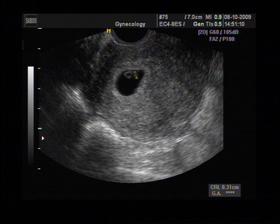

8/10 jsme se byli podívat u paní doktorky, zda testy nelhaly - a ono n e. Puclík měřil 0,37cm a co je důležité - srdíčko už funguje. Táta s Pepínem byli v ordinaci s námi, a když se na monitoru objevilo mimi, tak ho Pepíno pozdravil - udělal mu "ahoj" 🙂 oba nás to s Honzou dojalo. Další kontrola 22/10.